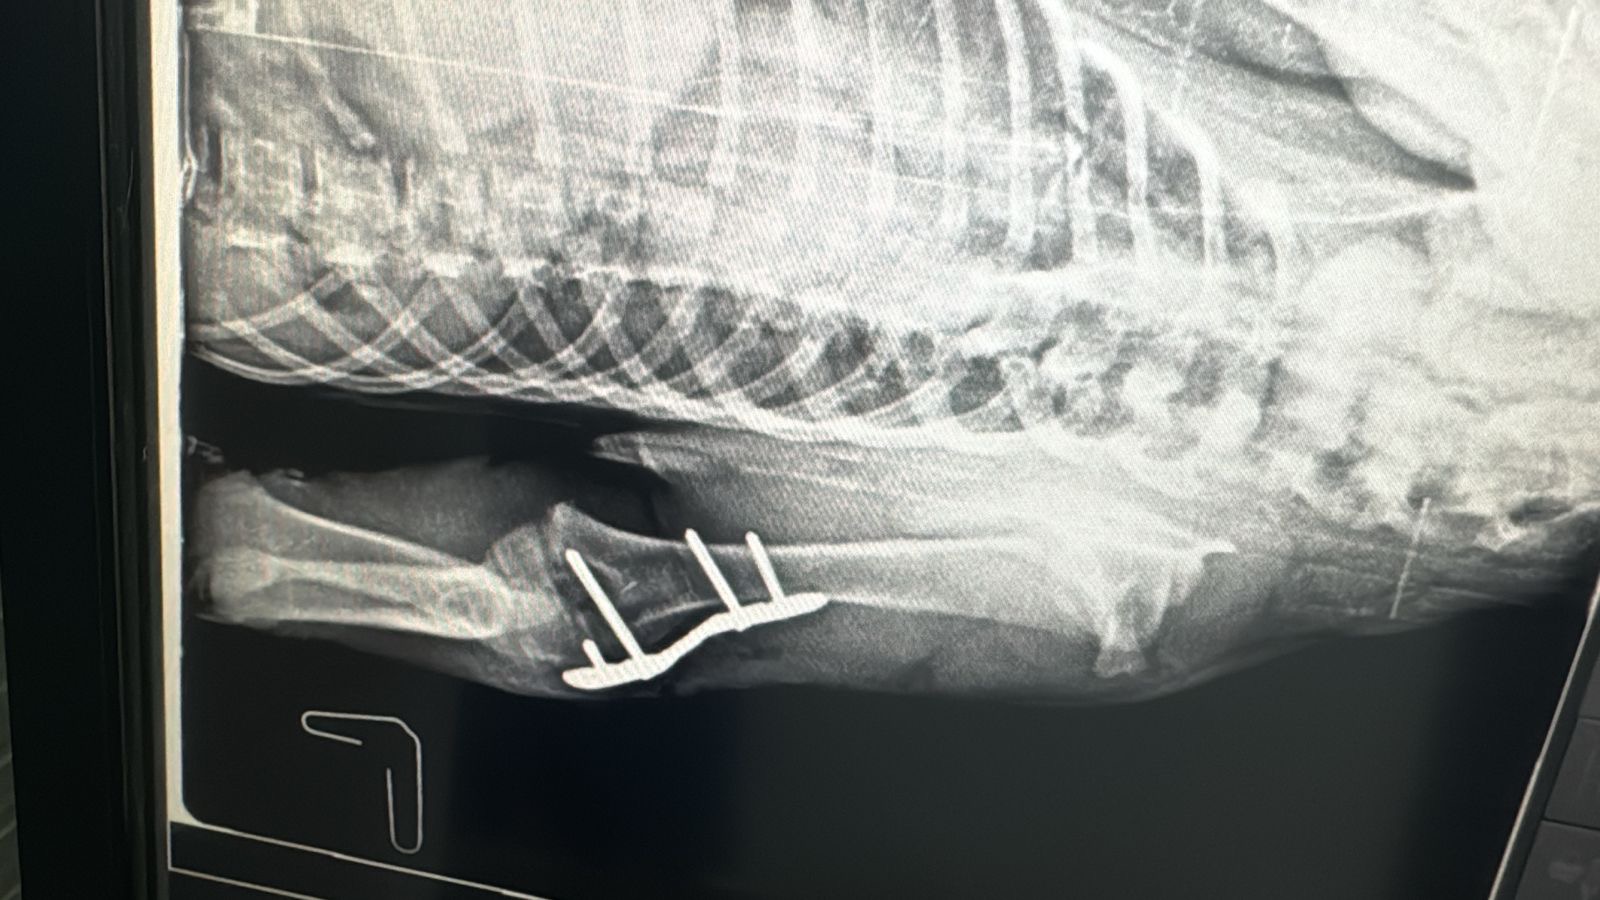

Legend was hit by a car, he had broken front and back legs. His recovery was long after 2 surgeries. He was rescued from the Chouf, laying on the side of the road under the rain. DOB: 24/8/2024